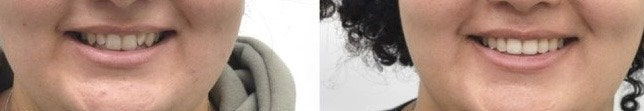

얼굴 사진을 보시면 교정이 마무리 되고

틀어져 있던 앞니의 치열이 가지런해졌을 뿐만 아니라

보다 정돈되고 예쁜 미소로 변화되었습니다 ^^

교정기간을 1년~1년6개월로 예상했지만

환자분 요청으로

6개월만에 교정을 마무리해드렸는데요

김승우 원장님의 섬세한 치료와 환자분의 협조도로

좋은 결과를 만들어낼 수 있었습니다^^